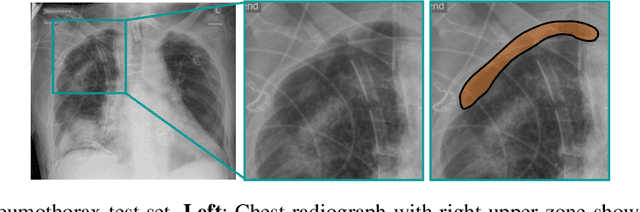

Abstract:The interpretation of medical images is a challenging task, often complicated by the presence of artifacts, occlusions, limited contrast and more. Most notable is the case of chest radiography, where there is a high inter-rater variability in the detection and classification of abnormalities. This is largely due to inconclusive evidence in the data or subjective definitions of disease appearance. An additional example is the classification of anatomical views based on 2D Ultrasound images. Often, the anatomical context captured in a frame is not sufficient to recognize the underlying anatomy. Current machine learning solutions for these problems are typically limited to providing probabilistic predictions, relying on the capacity of underlying models to adapt to limited information and the high degree of label noise. In practice, however, this leads to overconfident systems with poor generalization on unseen data. To account for this, we propose a system that learns not only the probabilistic estimate for classification, but also an explicit uncertainty measure which captures the confidence of the system in the predicted output. We argue that this approach is essential to account for the inherent ambiguity characteristic of medical images from different radiologic exams including computed radiography, ultrasonography and magnetic resonance imaging. In our experiments we demonstrate that sample rejection based on the predicted uncertainty can significantly improve the ROC-AUC for various tasks, e.g., by 8% to 0.91 with an expected rejection rate of under 25% for the classification of different abnormalities in chest radiographs. In addition, we show that using uncertainty-driven bootstrapping to filter the training data, one can achieve a significant increase in robustness and accuracy.